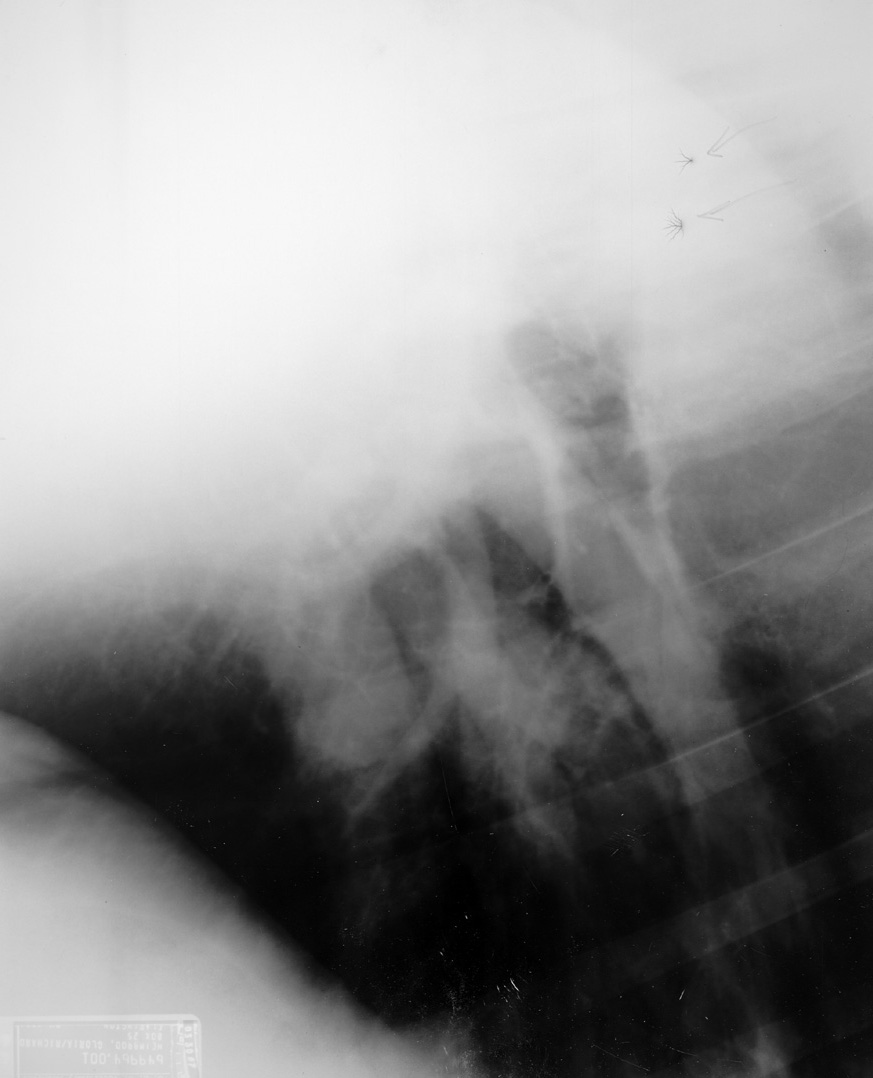

Click to enlarge Click to enlarge

Static

Static causes black branching artifact on the film due to exposure of the film to the elecrical spark of the static discharge.